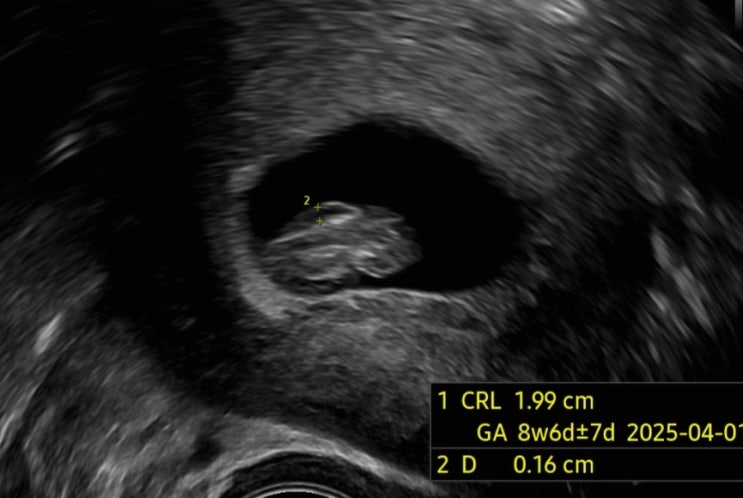

9주차 목덜미 투명대 후기

9주차에 병원을 방문했고 초음파로 잘 있나 확인하러 갔는데 의사 선생님께서 심각하게 수치를 많이 재시고...